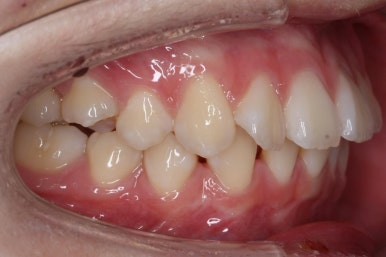

부산교정 키다리아저씨치과에 처음 내원하셨을 때의 입안 모습입니다.

윗니가 삐뚤어져 있고, 아래앞니 사이에는 틈이 듬성듬성 보입니다.

아랫니를 살펴보면 화살표 표시를 해둔 송곳니~송곳니 사이에 치아가 1개 모자랍니다. 원래는 4개의 앞니가 있어야 하는데, 3개 밖에 없었습니다. 이런 결손치아의 경우는 다음과 같은 문제가 생깁니다.

결손치아 부위에 틈이 생깁니다.

결손치아 주위 치아들이 제대로 서있지 못하고 기울어지게 됩니다.

위-아래 짝이 맞지 않아 중앙선이라든지 교합에 문제가 생깁니다.

이번의 경우 앞니가 하나 없는 경우여서 위-아래 앞니가 앞뒤로 간격이 멀어지게 됩니다.